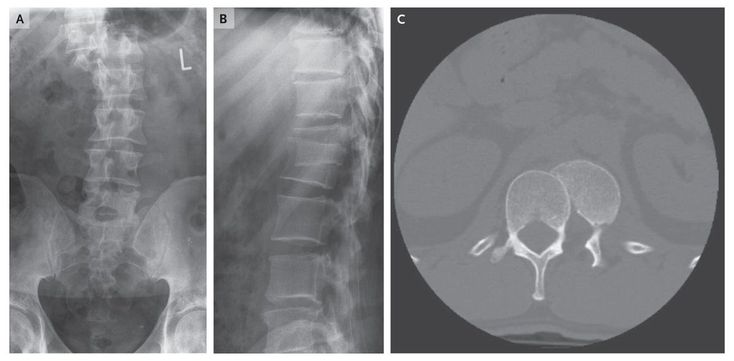

A 44-year-old man presented to the emergency department with severe pain after an accident at the gym. He reported he had been doing squats while balancing a 200-kg bar across his trapezius. His knee gave way and he fell to the floor, with the weight landing on his lower back. The patient managed to crawl out from under the weight but did not attempt to walk. On arrival at the emergency department he had full power in both lower limbs and normal sensation to light touch in all dermatomes of the lower limbs. The area over vertebral bodies T11 through L2 was exquisitely tender. Initial frontal and lateral plain films (Panels A and B, respectively) and an axial computed tomographic study of the area from T12 through L1 (Panel C) showed fracture–dislocation. The patient was taken to the operating room that night for open reduction and internal fixation of the fracture–dislocation of vertebral bodies T12 through L1. Postoperatively, he had preservation of normal neurologic function, with the exception of mild paresthesia on both sides of his trunk in a T12 dermatomal distribution. ✌️Baniaz 'jiz' Hospital and Company🤞 Health Care society https://t.me/drmohammedirfan